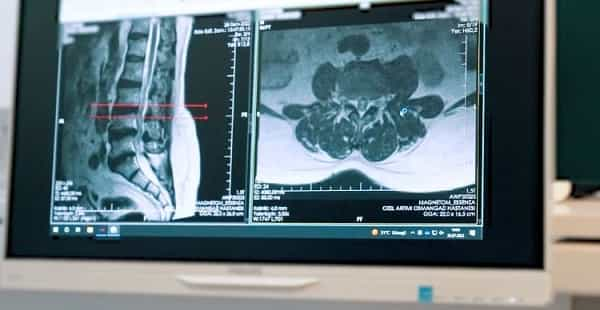

По прибытии в Стамбул Ричарда тепло и профессионально встретили в Turan Turan Health Group, доктор Юнус Уйсал . Первичная консультация с медицинской группой была тщательной и всеобъемлющей, поскольку они провели ряд тестов, чтобы определить основную причину боли в пояснице Ричарда. Благодаря четкому и краткому общению врачи разъяснили свои выводы, дав Ричарду возможность лучше понять свой диагноз и предлагаемый план лечения.